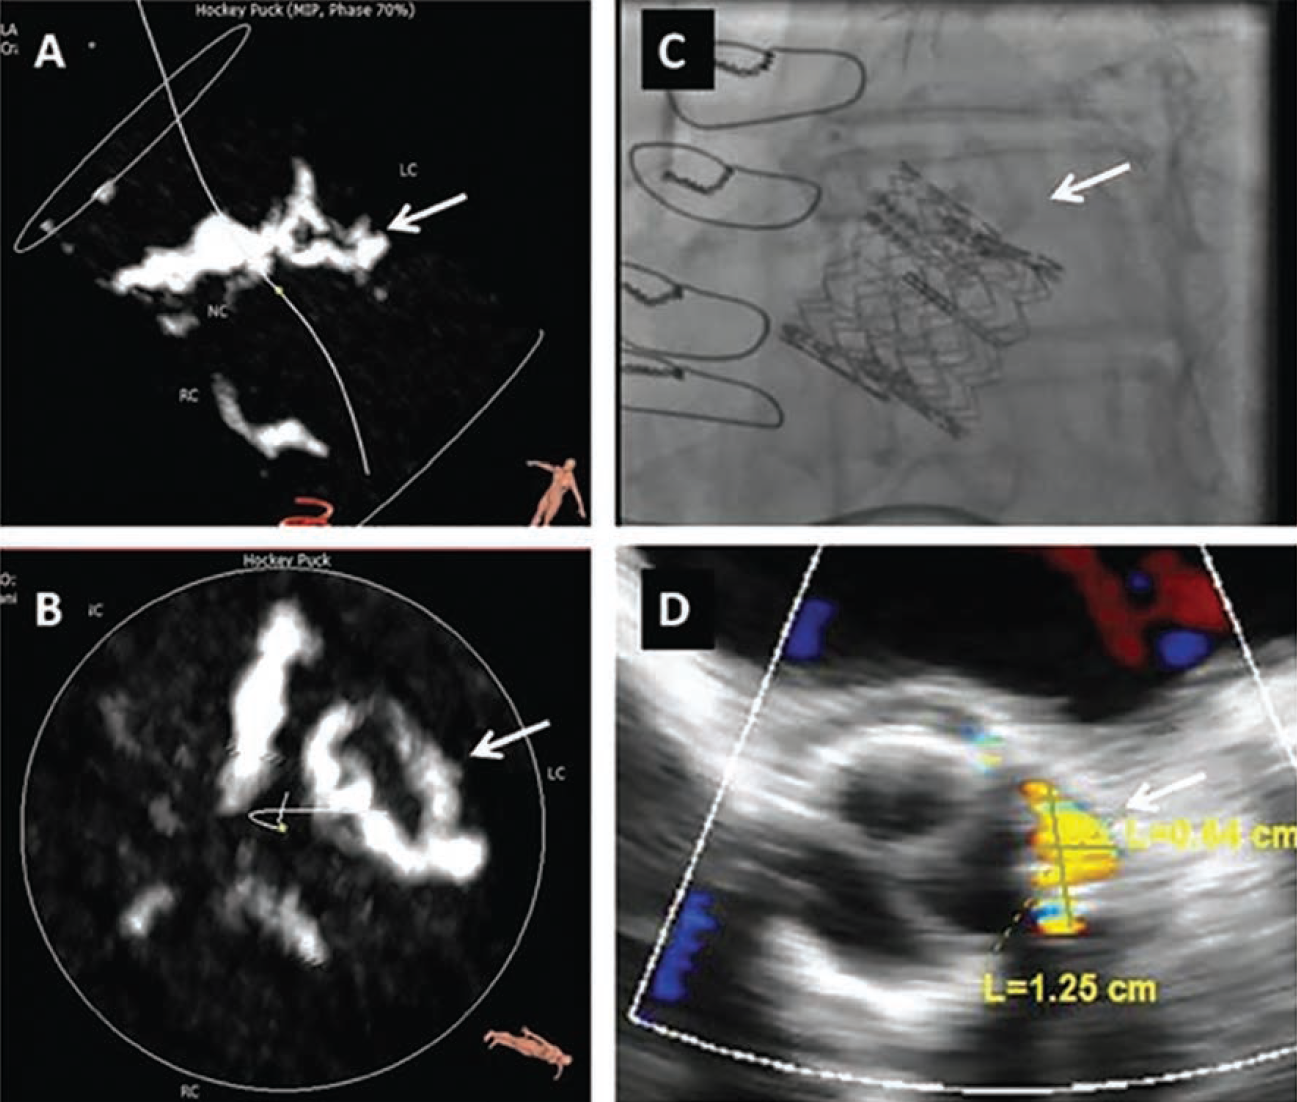

echocardiogram after TV-in-TV still showed the PVL (arrows indicate the location of calcification).

Reprinted with permission from Okuyama K, et ak. Percutaneous paravalvular leak closure for balloon-expandable transcatheter aortic valve replacement: a comparison with surgical aortic valve replacement paravalvular leak closure. J Invasive Cardiol. 2015 Jun;27(6):284-290.